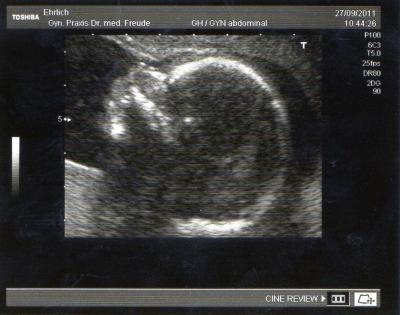

Da ich Blasenschmerzen habe , war ich schon heute anstatt Freitag bei meinen FA. Naja die Blase ist völlig okey , keine Harnwegsentzündung , nein die Füße unseres Babys massieren nur die Blase. Einen leichten Pilz habe ich , wobei er meinte das dieser in der Schwangerschaft häufiger vorkommt und dem Baby nicht schaden kann. Habe eine Salbe bekommen , das wird sich also legen. Und dann hat er nachgeschaut , wie es dem Baby allgemein geht. Wir bekommen ein Mädchen , also eine kleine Schwester für unsere grosse Tochter.

Bild zu VU mit Outing - Forum für Februar - Mamis